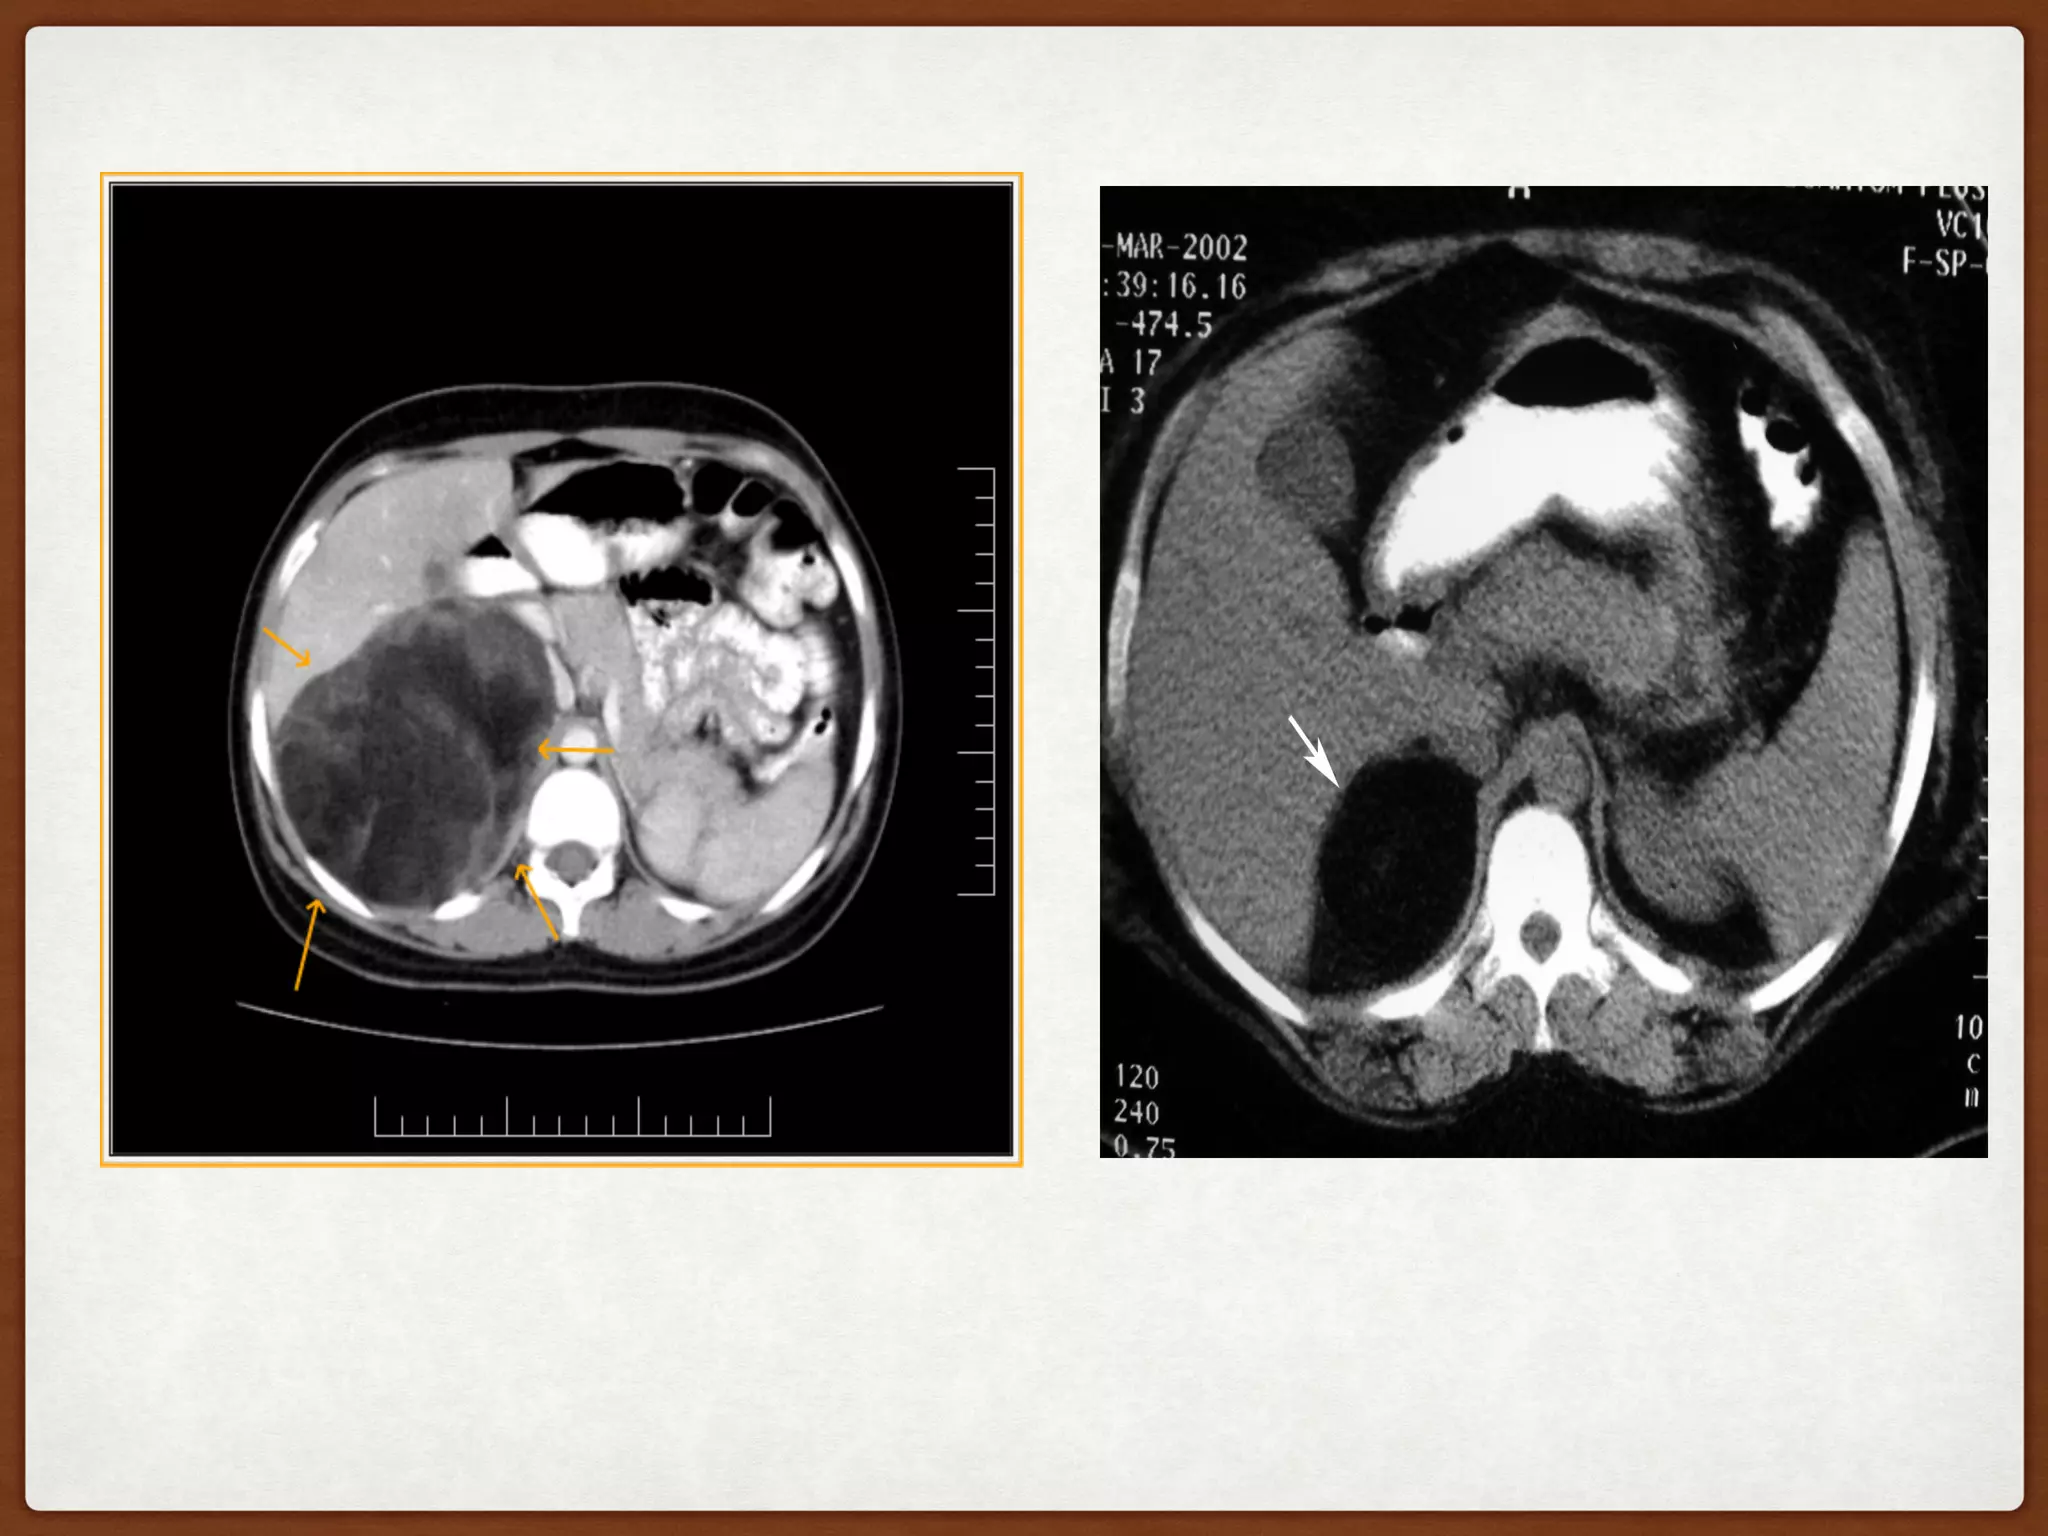

Fig : Myelolipoma with surrounding hemorrhage (A) CT scan shows a mass in the

right adrenal gland (large arrow) with surrounding hemorrhage (small arrows)

that was more predominant on sections obtained at lower levels. (B) T1-

weighted image (no fat saturation) at an identical unit shows hyperintense signal

corresponding to fat within the lesion. Areas of hemorrhage can be

differentiated from fat by comparing the appearances on non-fat saturation and

fat saturation images.